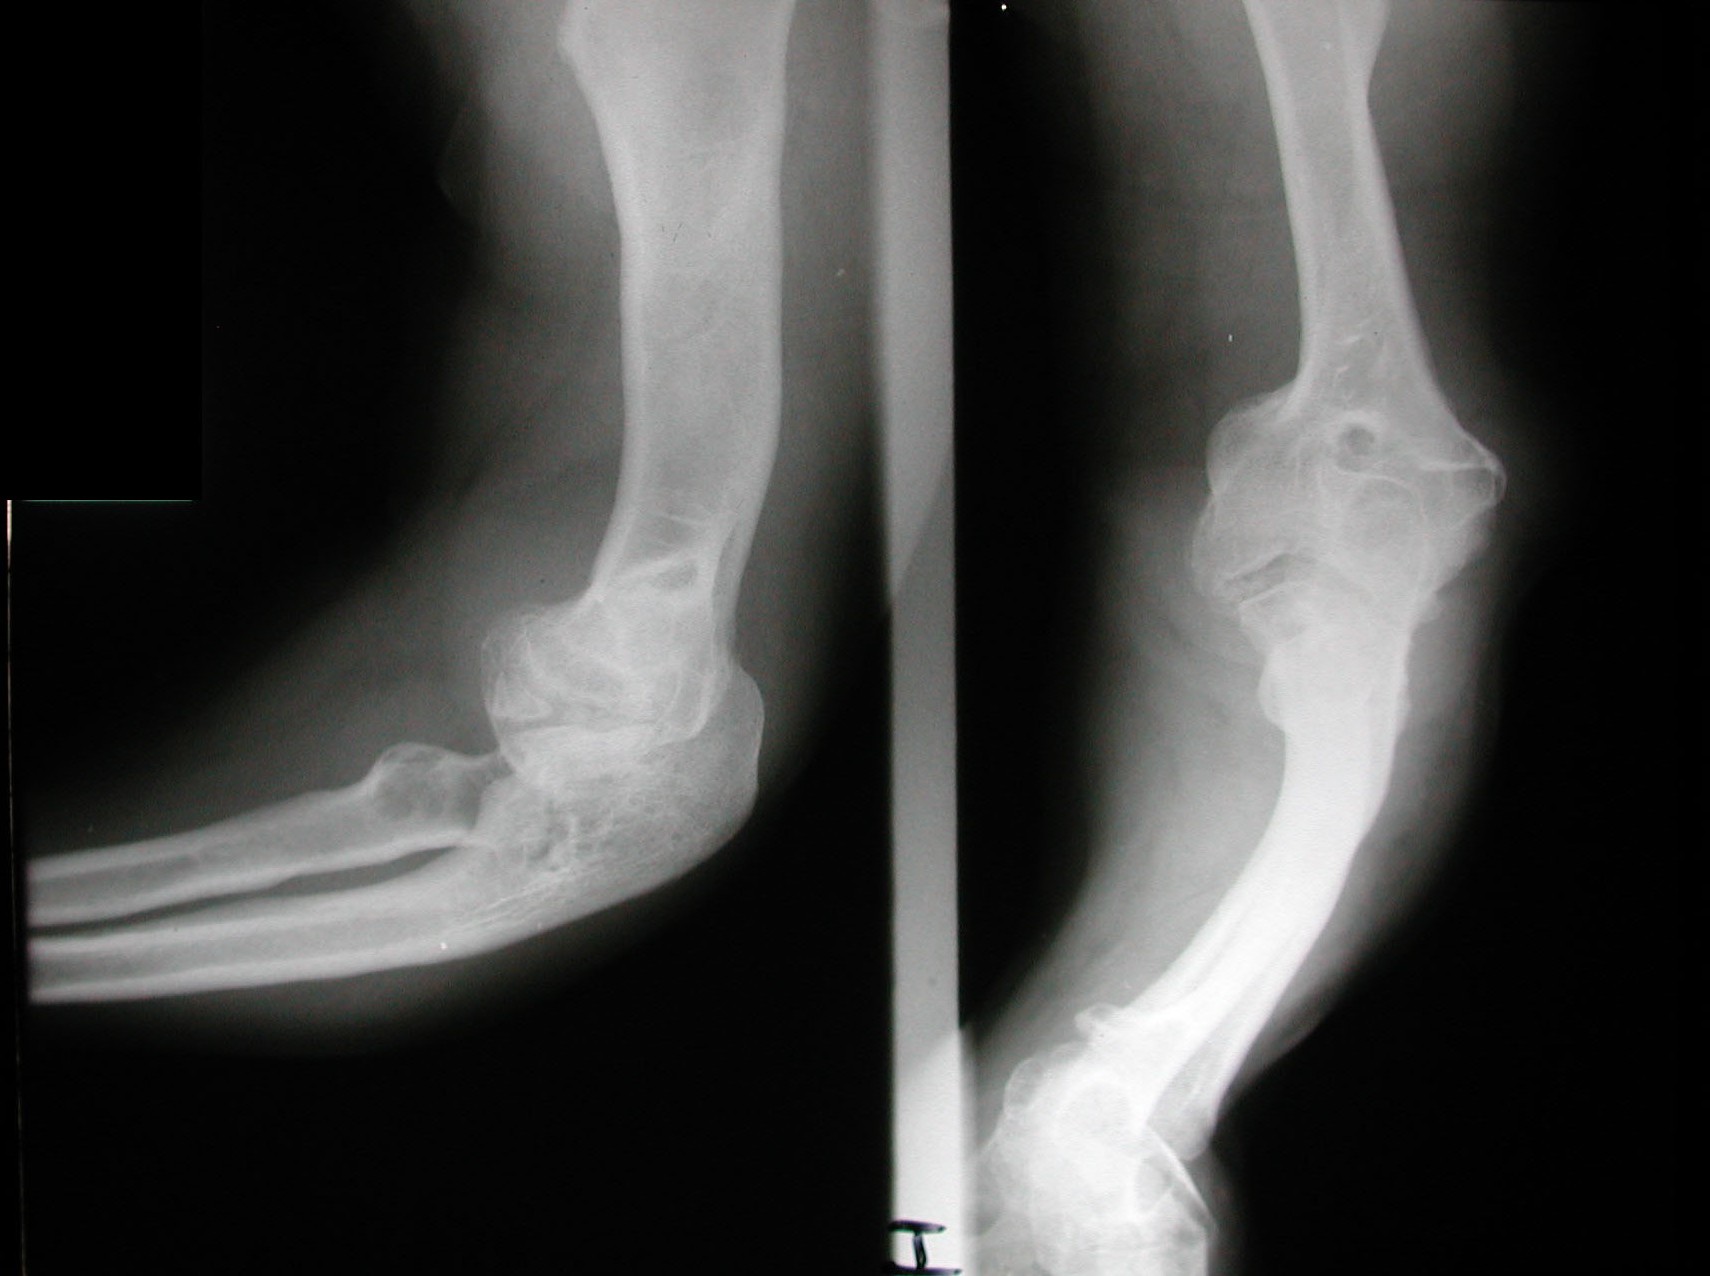

Seudoacondroplasia. [Pseudoachondroplasia]